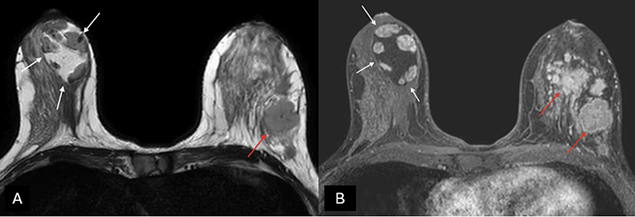

Magnetic resonance imaging (MRI)

MRI can be useful in establishing a diagnosis if suspicious features are noted on mammography or ultrasound [27]. Otherwise, MRI is not generally indicated for typical MH. On T1- and T2-weighted sequences (Figure 4), hamartomas appear as heterogeneously intense masses with glandular and fatty tissue components and a thin capsule [24]. Once the contrast media has been administered, MH exhibits a gradual, progressive enhancement with a type I time/intensity curve [28].

Figure 4. (A) Axial T2-weighted images and (B) T1-weighted fat-suppressed enhanced magnetic resonance imaging (MRI) – a capsulated, large-sized hamartoma can be seen located in the outer quadrants of the right breast, exhibiting a signal identical to normal mammary gland tissue, creating a “breast within a breast” appearance (white arrows). There are multiple masses in the contralateral breast with suspicious morphology, associated with a known invasive ductal carcinoma (red arrows). Image credits: El Yousfi Z, El Mansoury FZ, El Bakkari A, Omor Y, Latib R. Breast hamartoma with synchronous contralateral breast cancer: a case report. Cureus 2024; 16(8): e66534. DOI: 10.7759/cureus.66534. Reused under the terms of the Creative Commons Attribution License CC-BY 4.0. (https://creativecommons.org/licenses/by/4.0/deed.en).